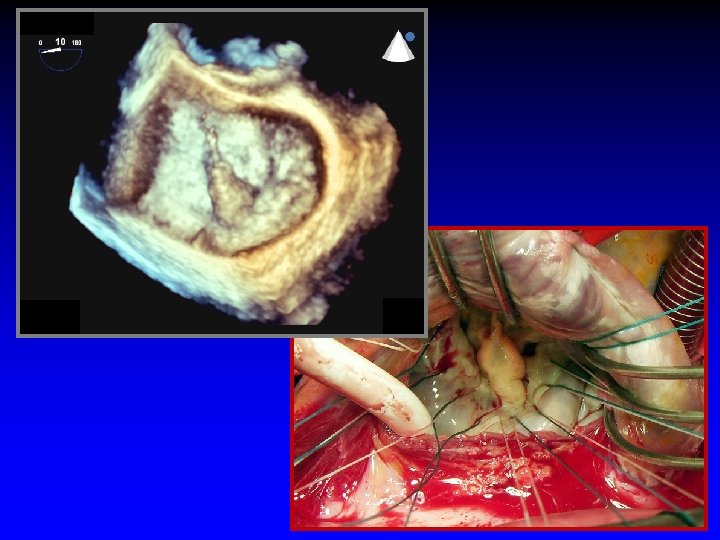

Case 3 Ruptured cords A 2 and A 3

Surgeon’s roadmap A 2 and A 3